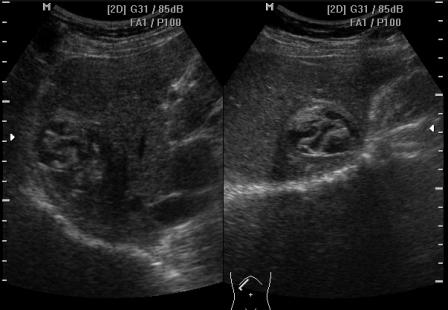

Спустя 8 месяцев повторный осмотр (после проведенного лечения):

ИФА на эхинококкоз. Отправляли кровь в ОблЦГЭ. 8 месяцев назад, когда выявили, титр был 1:200, сейчас 1:400.